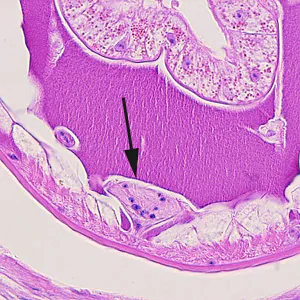

Larvae of Dioctotphyme renale in human tissue.

Identification of eggs in urine, or adult worms which are sometimes spontaneously expelled in urine. Adults may also be found during laparotomy or hysterectomy (or necropsy) when in the abdominal cavity. L3 larvae in subcutaneous nodules may be observed in stained tissue sections.